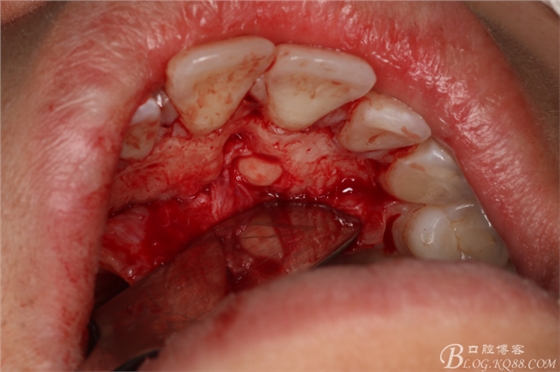

圖7.翻瓣

圖8.翻瓣暴露出鼻腭神經(jīng)管及腭側(cè)骨面

圖9.在切牙管旁邊去骨、暴露出21根尖區(qū)多生牙牙根

圖10.繼續(xù)去骨、發(fā)現(xiàn)多生牙部分位于鼻腭管內(nèi)